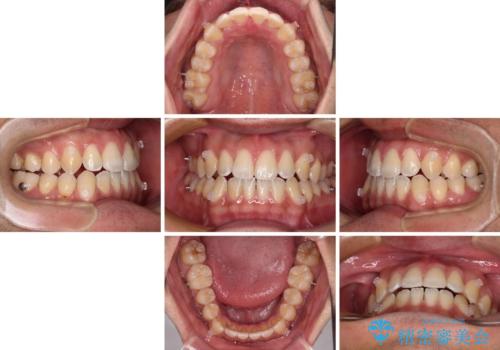

- 前歯のデコボコを気にして来院された患者様です。

歯列としてはワイヤー装置でもインビザラインでも対応可能でしたが、インビザラインが苦手とする上顎側切歯(真ん中から2番目の歯)の舌側転位が顕著でした。

治療の確実性を上げるために、インビザライン開始前に上顎のワイヤー装置にて舌側転位を解消し、その後インビザラインにて矯正治療を行うこととしました。

前歯のデコボコが早めに改善され、スムーズに治療を終えることができました。